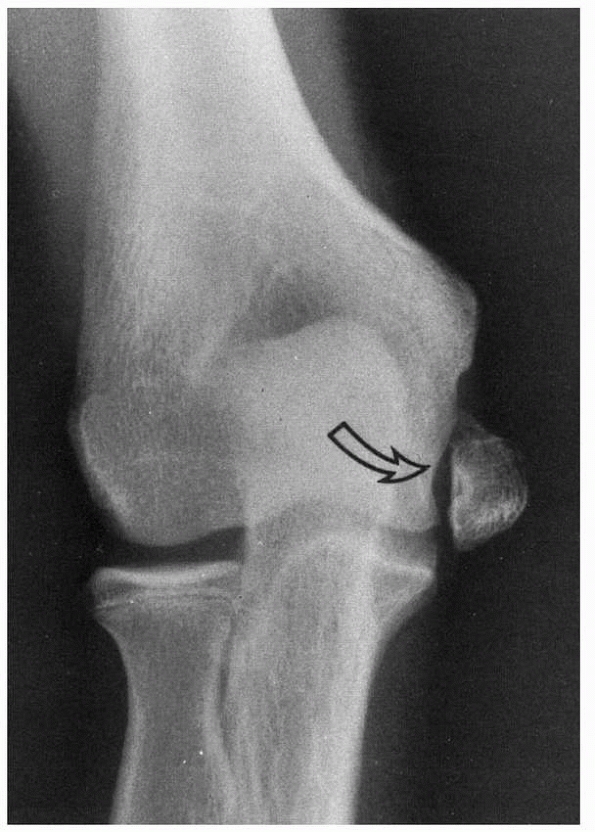

![]() |

FIGURE 15-1 A. Injury film of a 7-year-old with an undisplaced fracture of the lateral condyle (small arrows). Attention was drawn to the location of the fracture because of extensive soft tissue swelling on the lateral aspect (white arrows). B.

Because of the extensive soft tissue injury, there was little intrinsic stability, allowing the fracture to become displaced at 7 days (arrow). |